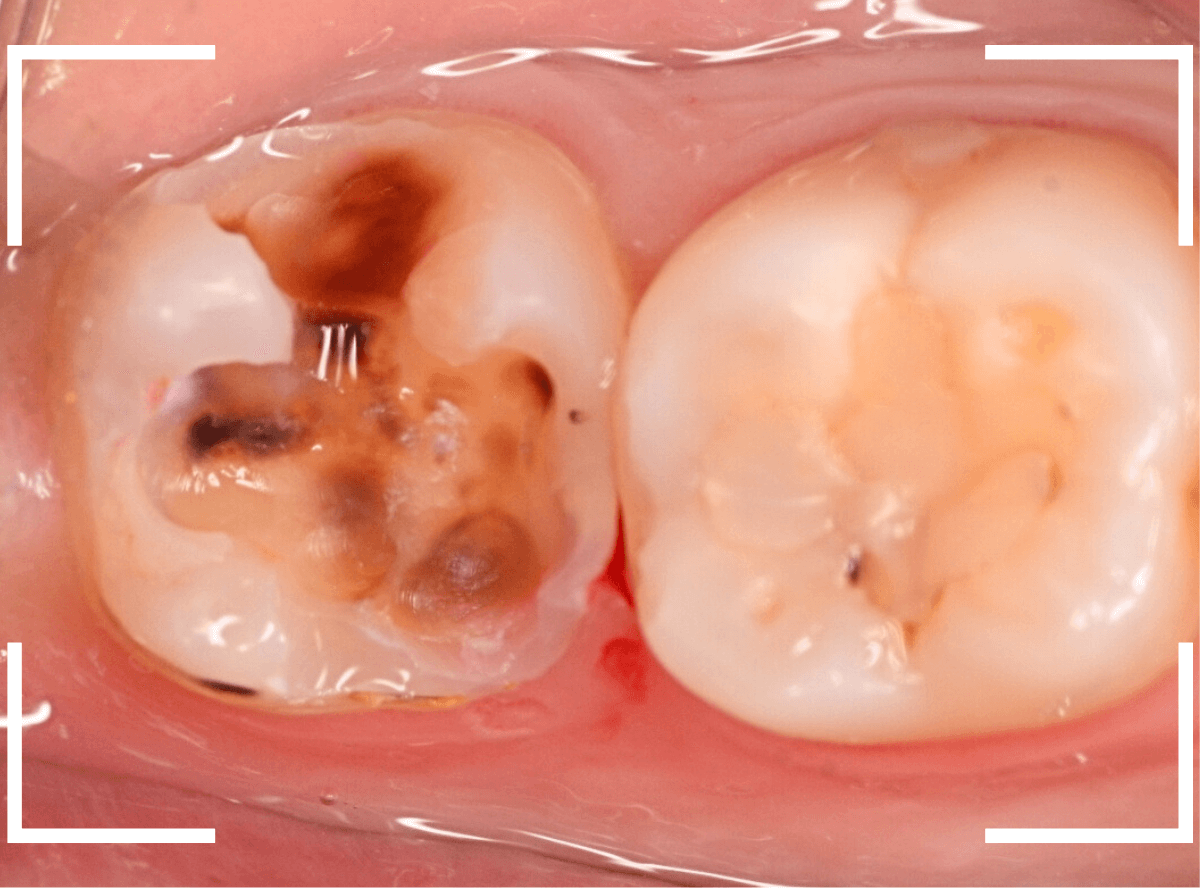

Case.8 大きな虫歯なのに、レントゲンではっきり写らない

こちらも定期検診希望で来院された患者さんです。

お口の中を拝見すると、明らかに虫歯がありました。

3本虫歯になっており、特に中央の小臼歯はかなり大きな虫歯になっているのが予想されます。

治療前にレントゲン写真で虫歯の大きさを確認するつもりが・・・あまりはっきり写ってきません。

患者さんに状況を説明して、歯を少しずつ削りながら虫歯を確認する事になりました。

まず、一番大きな虫歯と思われる部分を小さく削って確認します。

予想通り、虫歯が見えてきました。

隣りの奥歯と一緒に虫歯の治療を進めます。

色が染まっているところがまだ虫歯が残っている部分です。

2本とも、虫歯を全て取り切りました。

特に手前の歯はかなり広めの虫歯になっていました。

最終的に、手前の虫歯の除去も終わったところです。

手前の歯の虫歯は中央の歯まで達していました。

このように明らかに大きな虫歯があると診断されるような状況でも、レントゲン写真でうまく診断できない場合もあります。